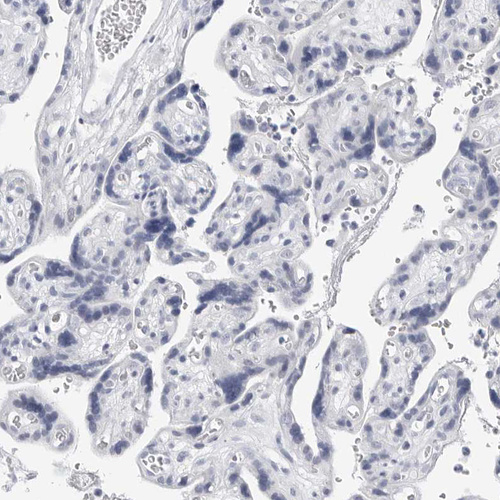

Immunohistochemistry analysis in human heart muscle and placenta tissues using HPA026900 antibody. Corresponding PLN RNA-seq data are presented for the same tissues.